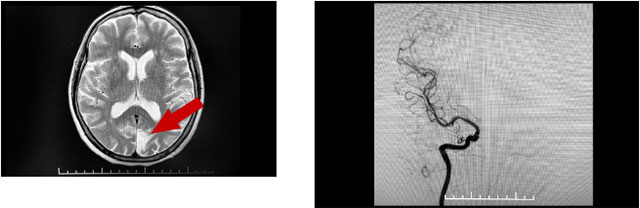

吴阿姨有高血压病史,头晕断断续续也有十多年了,此前在外院曾查出腔隙性脑梗死。张静波主任对其进一步完善了影像学检查发现,患者左侧枕叶皮层部位有陈旧性梗死,为了明确脑梗死的病因,对患者进行了全脑血管造影(DSA)检查,发现患者多发小血管病变,头晕症状考虑多发血管狭窄造成低灌注导致。

检查中还发现,其右侧颈内动脉床突段有一动脉瘤,有破裂风险,是一枚“不定时炸弹”。综合来看,患者同时存在缺血和出血两种危险因素,应尽快干预治疗。

▲ 完善检查发现梗塞和动脉瘤